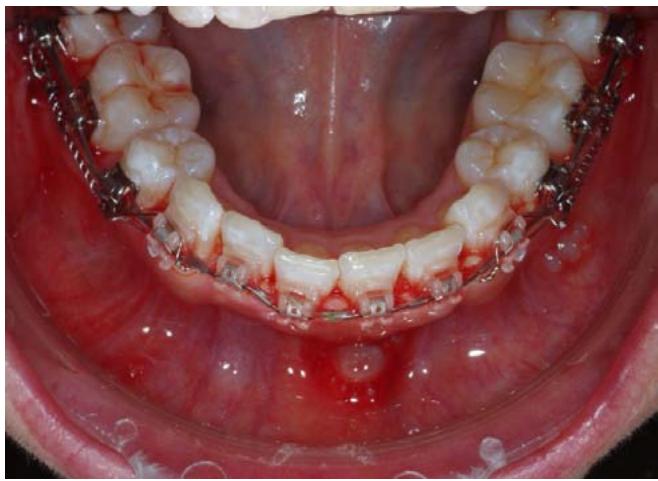

Les ancrages seront mis en place le jour de la pose des attaches et connectés immédiatement aux canines mandibulaires avec des ressorts NiTi de 300g des deux côtés.

Une chainette élastique est mise en place de 33 à 43 afin d'éviter de voir apparaitre des diastèmes entre les dents antérieures lors du recul. Le recul se fait en masse sans aucun effet parasite car la direction de traction est dans l'axe du fil inférieur. La chainette sera changée tous les mois lors des RDV de la paciente.

Vue du système de traction du côté droit, gauche, puis en vue occlusale.